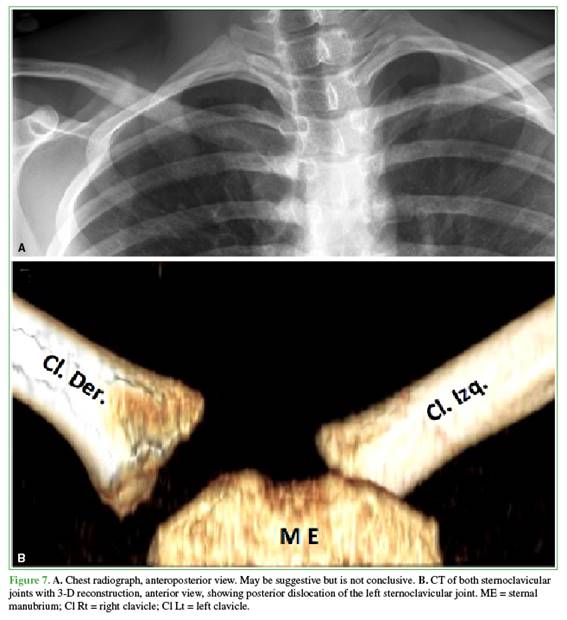

Diagnosis is challenging because of rarity and variable signs and symptoms, so the condition is often over-looked. Diagnostic suspicion based on trauma history, a careful physical examination, and appropriate imaging is essential.2,3 Radiographs are difficult to interpret due to overlapping structures and are often inconclusive (Figure 7A). CT is the most useful diagnostic tool because it visualizes the joint injury and involvement of cervical and mediastinal structures (Figure 7B). MR angiography helps characterize possible vascular injuries (Figure 1C).